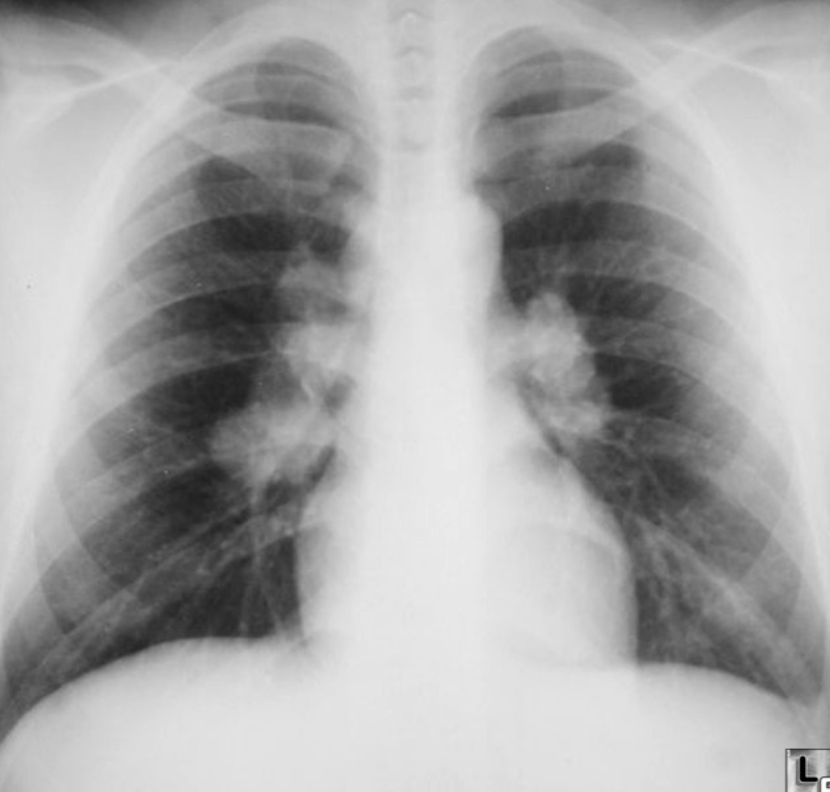

A 32 years old male presented with history of low grade fever, cough with sputum, sometimes blood stained. He has weight loss of 5 kg during this period. His chest X-Ray is shown ABOVE.

Describe the abnormality seen in the X-Ray?

- Cavitation and consolidation in the left upper lung

- bilateral Hilary lymphadenopathy

What is the likely diagnosis? Pulmonary TB

Mention 2 other investigations which you will advise?

- o Sputum culture and smear

- o IGRA

Mention 2 factors which increase the risk of this disease?

- HIV

- Chemotherapy

Mention 2 drugs used to treat this medical condition?

- o Rifampicin

- o INH (Isoniazid)